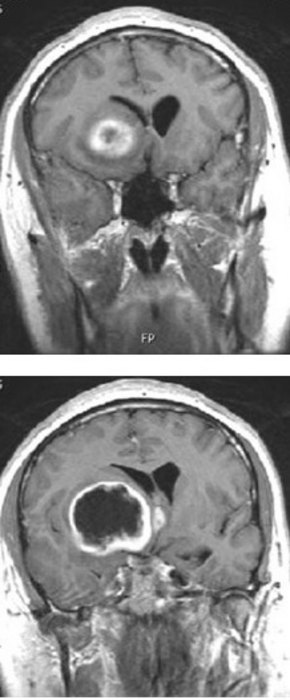

UT Southwestern researchers have identified a molecular pathway responsible for the spread of glioblastoma to surrounding tissue in the brain, as well as an existing drug that curbed tumor growth in animal models. The findings, published in Nature Cell Biology , have led to a clinical trial that could offer new hope to patients with glioblastoma, the most common form of brain cancer in adults that kills hundreds of thousands of people worldwide each year.

Despite decades of research, the prognosis for most patients with glioblastoma remains dismal, with a median survival after diagnosis of just 15-18 months. Part of the challenge in treating this cancer is its invasive nature: Glioblastoma tumors invade surrounding healthy brain tissue, sending tentacle-like extensions out from the primary tumor that are impossible to remove with surgery alone and difficult to reach with chemotherapy.

In the new study, Dr. Habib and colleagues in the Habib lab and elsewhere showed that when cells with amplified EGFR were stimulated with ligands, this receptor appeared to act as a tumor suppressor, preventing invasion into healthy tissue both in laboratory and animal models. Further experiments showed that a cytoskeletal protein called BIN3 appears to be responsible for inhibiting this invasion. When the researchers dosed animals with amplified EGFR glioblastoma tumors with an FDA-approved arthritis drug called tofacitinib that increases the amount of EGFR ligands and BIN3, tumors remained smaller and were less likely to invade healthy brain tissue. Additionally, these animals survived significantly longer than animals that didn’t receive this drug.